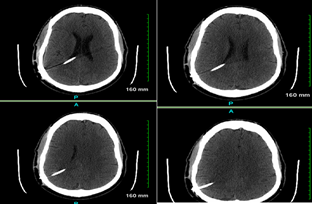

Figure 1: CT Head with and without contrast

A right posterior parietal approach shunt extending though the lateral ventricle with its tip at the posterior midline in the upper third ventricle. Ventricular system appears to be decompressed. The intracranial and extracranial shunt tube appears to be normal.